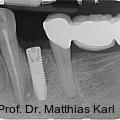

Parallel zur Entwicklung verkürzter Behandlungskonzepte haben sich auch die Außengeometrien zahnärztlicher Implantate hin zu aggressiveren Gewindeformen und konischen Grundkörpern entwickelt. Fotos: © Prof. Dr. Matthias Karl